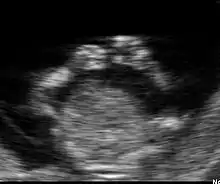

Embryon à 8 semaines

L'embryon mesure entre 15 et 22 mm. La vésicule vitelline qui le nourrit est juste à côté. À la fin de cette semaine, les coudes deviennent visibles